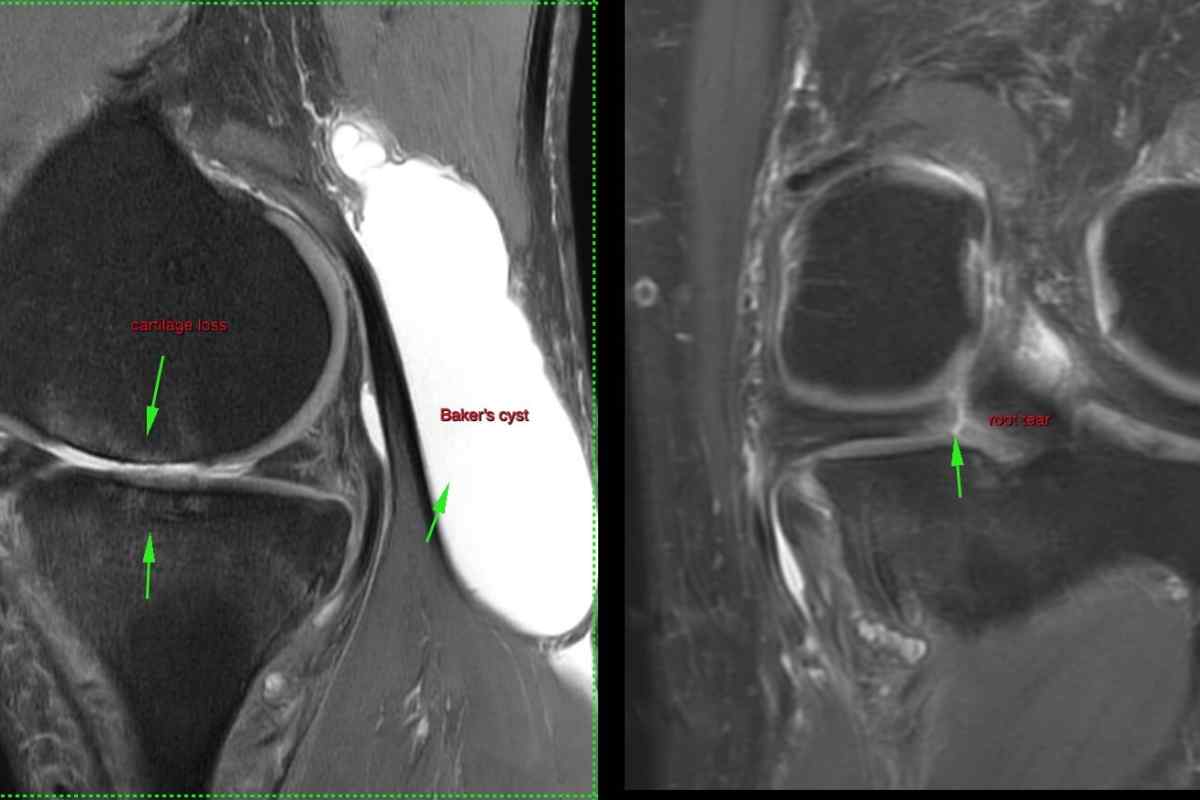

Фото и диагностика кисты Бейкера